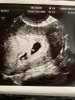

Ja już dawno po wizycie ale musiałam dojść do siebie

Widziałam wszystko na co liczyłam tylko podwójnie

Będę mieć bliźniaki

jestem nadal w szoku. Muszę znaleźć sobie nowego (drugiego?) lekarza, bo Luxmed nie prowadzi ciąż mnogich (chociaż w zaleceniach po wizycie napisał że „nie zaleca prowadzeni ciąży w Luxmed”). Wrocławianki, znacie jakiegoś dobrego lekarz prywatnego?

W ogóle byłam w takim szoku że kilku pytań mu nie zadałam

muszę chyba wbić się na teleporade.

Załączniki